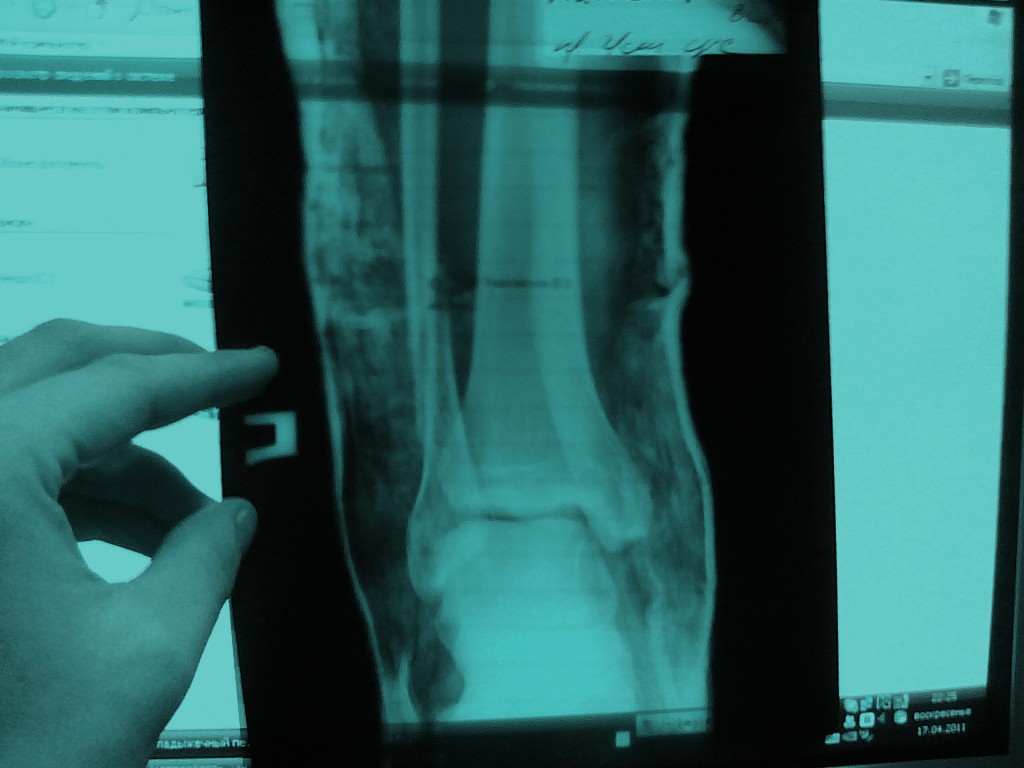

Закрытый трехладыжечный перелом костей правой голени со смещением костных отломков

Доброго времени суток. 30 марта 2011 года, подвернул правую ногу, почувствовав в последствии сильную боль и смещение кости. поехал сразу в травматологию-положили в больницу. Выписали на амбулаторное лечение 5 апреля 2011. Сейчас хожу дома на костылях без нагрузки в гипсе, наложенном на лангетку.Хотел бы узнать как скоро можно будет вернуться к полной нагрузке на ногу.снимки прилагаются.

Хотелось бы увидеть боковую проекцию, но обычно притаких повреждениях гипсовая иммобилизация накладывается на 2,5 месяца, затем ЛФК, физиолечение с восстановлением функции в голеностопном суставе и постепенное увеличение нагрузки. Работоспособность, в зависимости от специальность, восстанавливается от 4 до 6 месяцев. В нашем отделении, при отсутствии противопоказаний, выполняется оперативное вмешательство